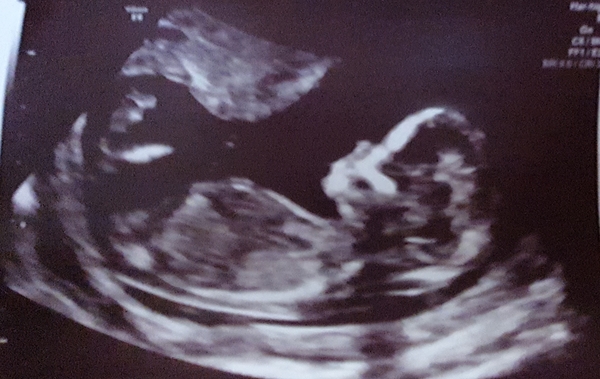

@Pe4nutsmum Maybe mine isnt a good/clear picture now looking at yours because I still cant see any nub or maybe I'm just going blind who knows! Heres the little one at nearly 14 weeks